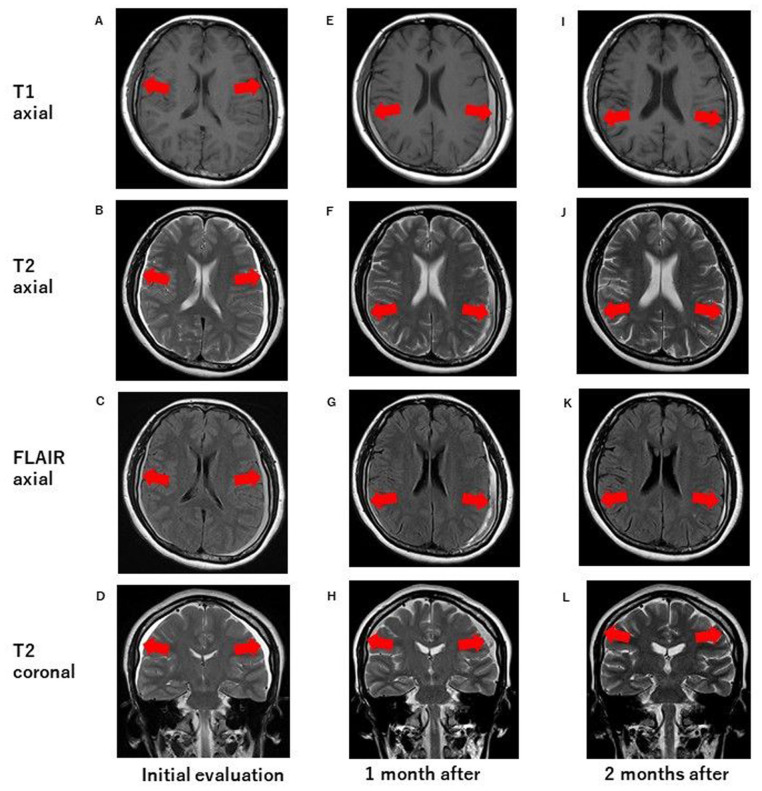

颈椎病常用颈椎牵引疗法;然而,并发症,如硬膜下血肿可发生。可能的机制包括脑脊液(CSF)渗漏和桥静脉损伤。一位51岁的日本妇女在接受颈椎牵引治疗2周后出现持续性头痛。磁共振显示双侧硬膜下血肿。卧床休息、口服镇痛药和每日输注治疗均未能改善症状,但2次硬膜外血贴可使患者恢复。虽然没有发现直接的脑脊液渗漏,但脊髓硬膜外病变可能是原因之一。颈椎牵引治疗可通过颅内低血压引起硬膜下血肿。临床医生应考虑到这种风险,并对受影响的患者进行彻底的诊断评估。

Cervical traction therapy is commonly used for cervical spondylosis; however, complications, such as subdural hematomas can occur. Possible mechanisms include cerebrospinal fluid (CSF) leakage and bridging vein damage. A 51-year-old Japanese woman developed a persistent headache after 2 weeks of cervical traction therapy. Magnetic resonance imaging revealed bilateral subdural hematomas. Bed rest, oral analgesics, and daily infusion therapy failed to improve symptoms, but 2 epidural blood patches led to recovery. Although no direct CSF leakage was found, a spinal epidural lesion may have contributed. Cervical traction therapy may cause subdural hematomas via intracranial hypotension. Clinicians should consider this risk and conduct thorough diagnostic evaluations in affected patients.